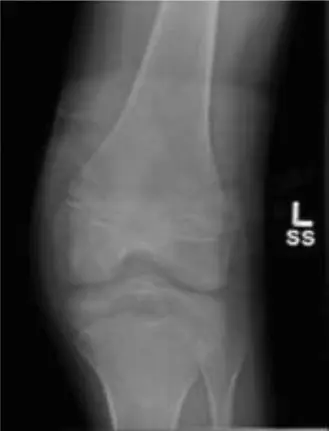

المنظر الأمامي الخلفي (AP View):

يظهر بوضوح كسرًا اقتلاعيًا في الشوكة الظنبوبية، يشمل المنطقة بين اللقمتين. قد يظهر الجزء المكسور نازحًا جزئيًا إلى الجانب العلوي.

المنظر الجانبي (Lateral View):

يقدم معلومات حاسمة حول الإزاحة الأمامية والهجرة العلوية للجزء المكسور. هذه الصورة ضرورية لتقييم درجة النزوح.

الشكل 1: صورة بالأشعة السينية الجانبية قبل الجراحة تظهر كسرًا نازحًا في الشوكة الظنبوبية، مع هجرة الجزء المقتلع إلى الأعلى والأمام.